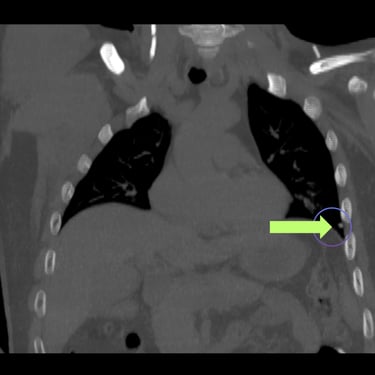

La hidrocefalia puede complicarse cuando la derivación ventrículo-peritoneal deja de funcionar correctamente, produciendo aumento de la presión intracraneal y síntomas como cefalea, vómitos, somnolencia o deterioro neurológico. Cuando el peritoneo deja de ser una opción viable debido a infecciones, cirugías previas o mala absorción, se considera la derivación ventrículo-pleural como alternativa efectiva. Este procedimiento permite redirigir el líquido cefalorraquídeo hacia la cavidad pleural, donde puede ser absorbido adecuadamente. La intervención oportuna restablece el drenaje del LCR, reduce la presión intracraneal y mejora el pronóstico del paciente, siendo una solución segura en casos de disfunción peritoneal.